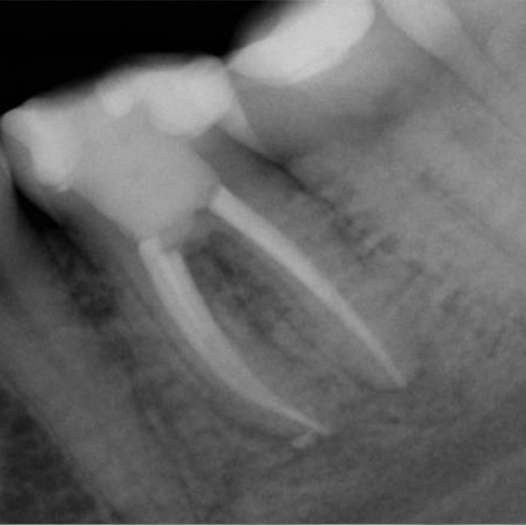

Before

Before Root Canal treatment